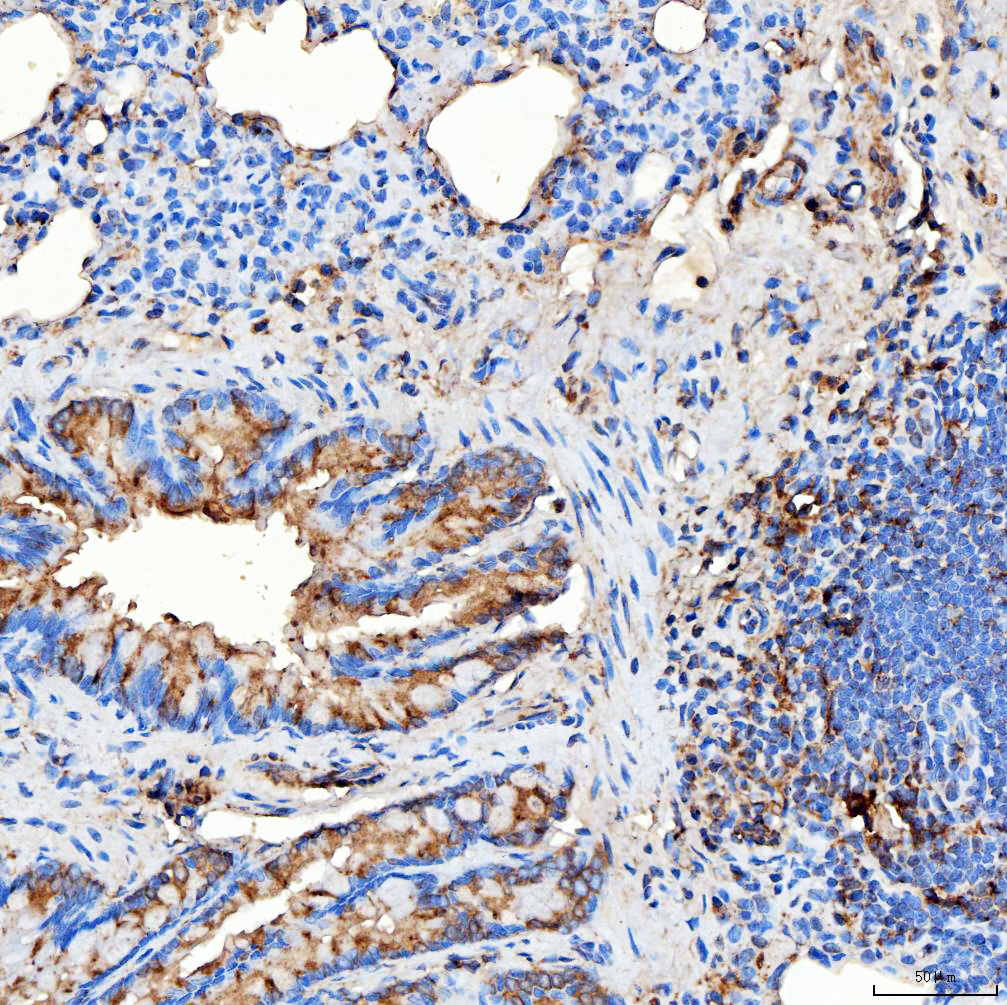

IHC analysis of RAB7A using anti-RAB7A antibody (A02409-1).

RAB7A was detected in a paraffin-embedded section of human endometrioid adenocarcinoma tissue. The tissue section was incubated with rabbit anti-RAB7A Antibody (A02409-1) at a dilution of 1:200 and developed using HRP Conjugated Rabbit IgG Super Vision Assay Kit (Catalog # SV0002) with DAB (Catalog # AR1027) as the chromogen.